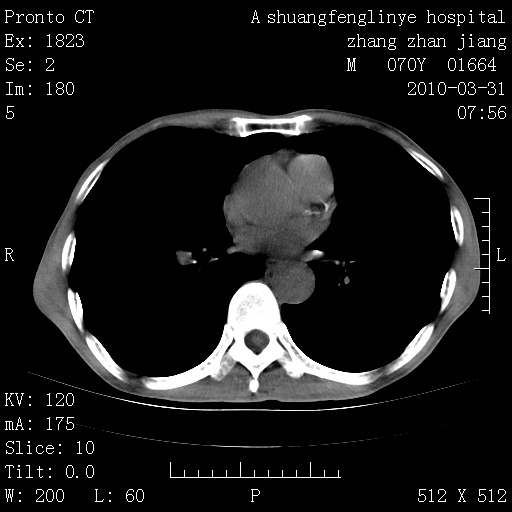

双上肺继发型tb并左上空洞形成,主动脉冠脉钙化。

1)两肺上叶继发性肺结核并左肺上叶空洞形成。2)冠状动脉及主动脉钙化。